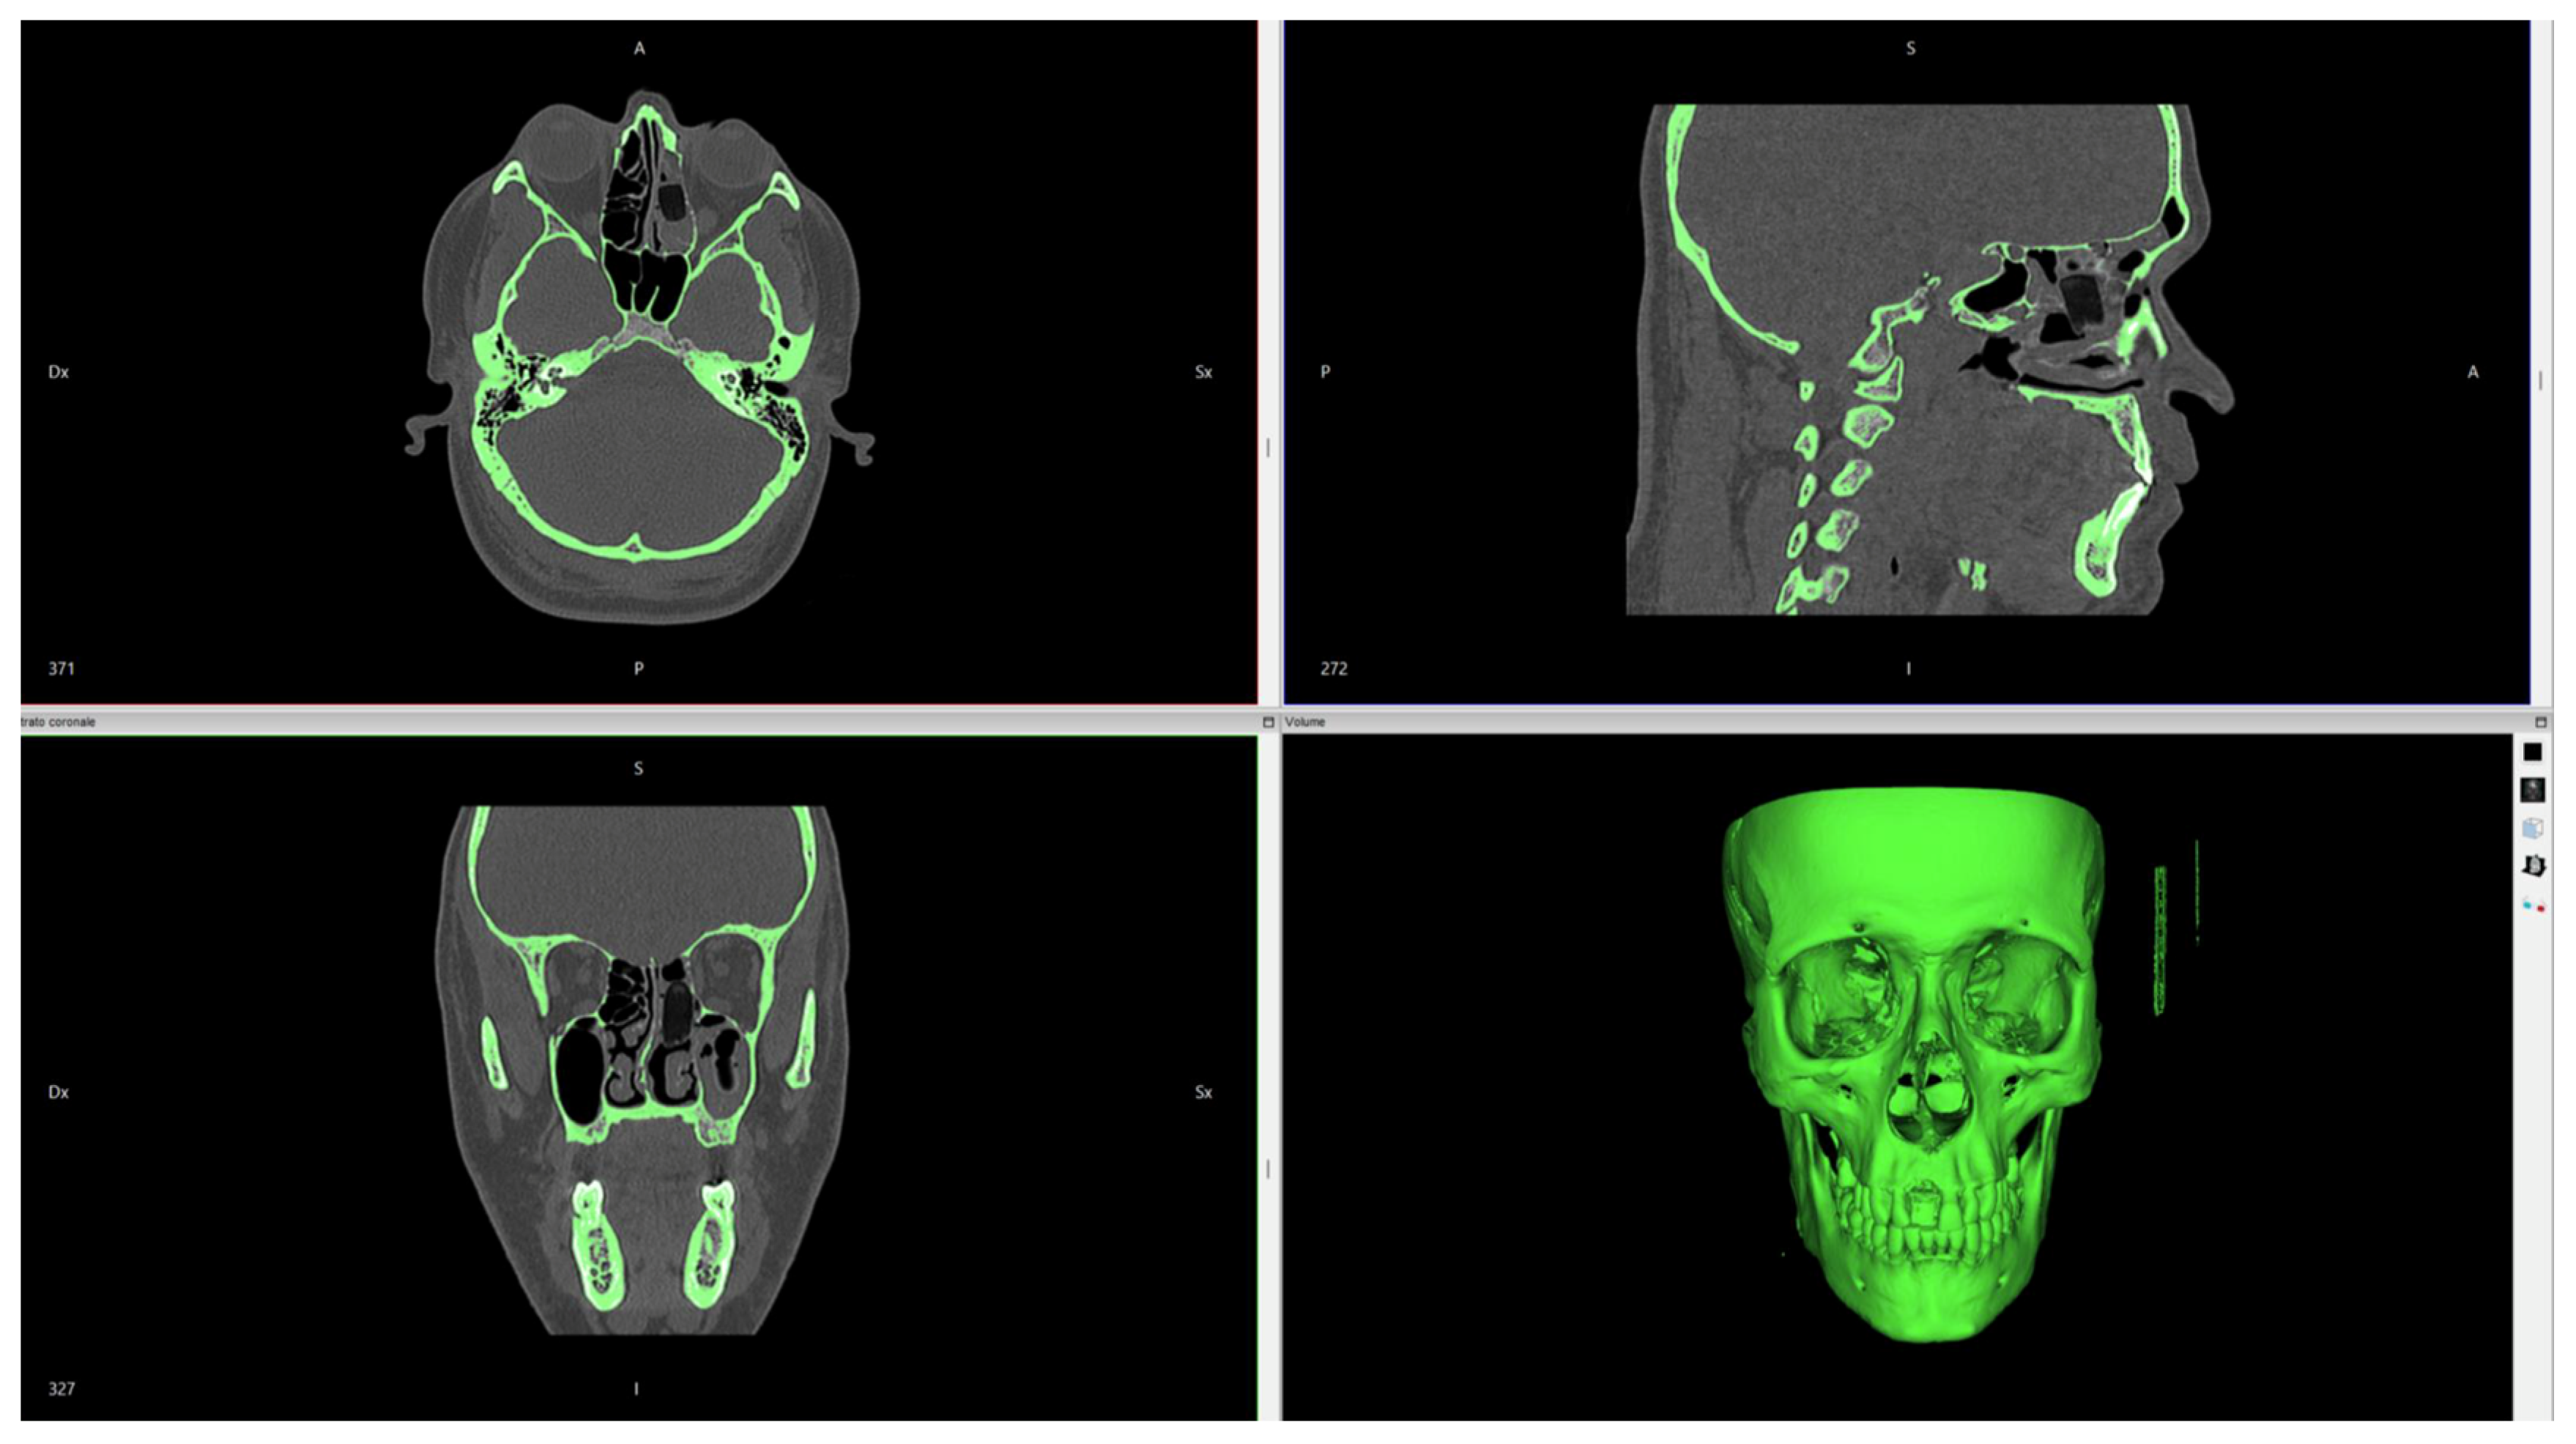

Figure 2. Invesalius software digital workflow. The imported file DICOM is transformed into a 3D image.

The workflow process is shown in Figure 2, Figure 3, Figure 4 and Figure 5.

2.4. Post-Surgical Immediate Evaluation